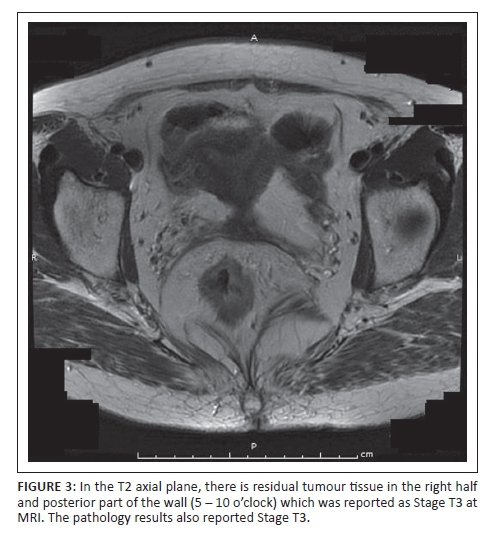

According to post-neoadjuvant therapy MRI scan staging, 3 patients were Stage 0, 5 patients were Stage 1, 13 patients were Stage 2a and 14 patients were Stage 3b. The postoperative pathology staging is summarised in Table 6. The results show, according to the TNM staging system, that in a total of 35 patients, 13 cases (37.14%) were overstaged (Figure 1a and b), 3 cases (8.57%) were downstaged (Figure 2) and 19 cases (54.28%) were correctly staged (Figure 3). Reasons for overstaging include fibrosis, desmoplastic reaction and lymphoplasmocytic infiltration. A reason for downstaging may be that MRI cannot differentiate tumour tissue. The accuracy of MRI in the overall staging according to the TNM staging system was 28%.